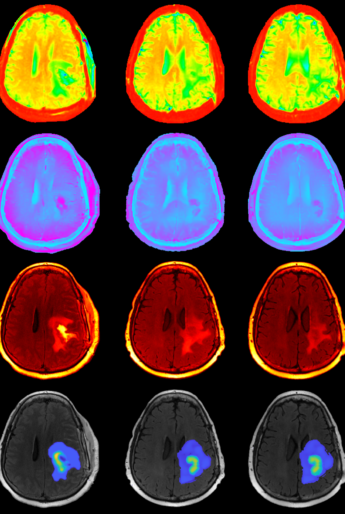

This figure shows diffusion weighted, magnetic resonance imaging data (top three rows) used to estimate the extent of tumor burden and tumor cellularity for each patient. These images are then used to personalize predictive models of tumor growth and response (bottom row).

In a paper published in Nature Scientific Reports, the authors used a combination of anatomical and structural imaging to inform a computational mechanistic model that predicts for high-grade glioma tumor progression.